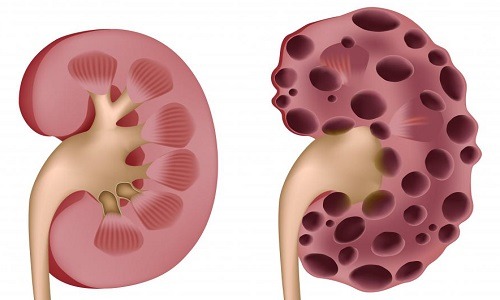

要知道,肾囊肿虽然是一个良性的囊肿,但这个良性囊肿是会持续发展的。我临床上遇到的肾囊肿患者在做复查时,身体都会出现一些很不舒服的症状,如腰酸、尿路感染、血尿、发热等。做了B超复查后,也会发现肾囊肿的体积长大了,这其实都是因为肾囊肿过大, 压迫到肾脏或出现梗阻,引发的一系列并发症表现。

一旦肾囊肿大于4厘米,压迫肾脏,就会影响到肾功能,造成患侧肾功能受损,患者会出现腰酸腰痛、乏力、腹胀、尿蛋白、血肌酐升高、尿素氮升高。而我们的肾脏有两个肾,没有患肾囊肿的一侧肾脏,会代偿患侧受损的肾脏,如果这时肾囊肿患者没有做好定期复查,就很难及时发现肾脏受损,一旦受损严重,还会导致肾衰竭。

我有一位肾囊肿患者,他最初是右侧肾长了一个囊肿,体积2厘米,无症状,也没当回事。一年过去了以后,患者发现自己总觉得乏力、腰酸,在一次体检后,发现自己血肌酐升高了,还检查出了尿蛋白(+),右肾囊肿从一个长到了3个,最大的已经长到了3厘米,左肾也被查出了囊肿,也是多发囊肿,最大的长到了2厘米。这位患者被确诊为多发性肾囊肿、肾功能不全。